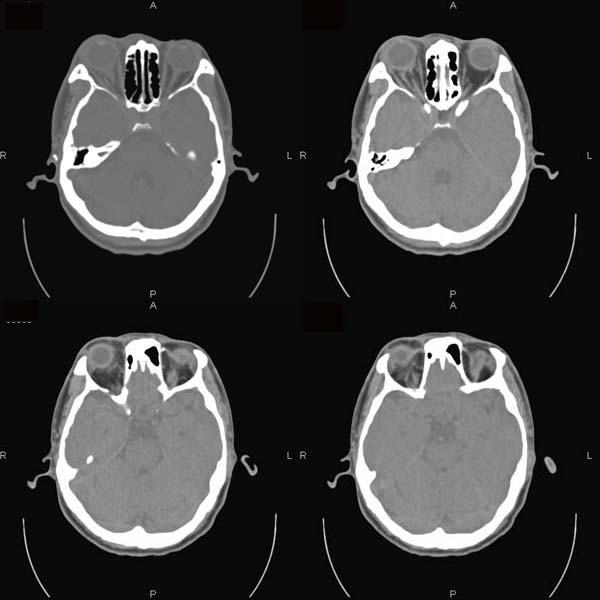

以下是引用逸风在2006-6-5 17:45:00的发言:[br]ct显示:右侧眼球轻度突出,眼环增厚,球后脂肪间隙模糊,可见点状高密度灶,同侧视神经稍增粗,周围眶壁骨质未见明显异常,眼环完整,球内未见明显异常密度.[br]诊断意见:1.右侧眼球钝挫伤合并球后间隙出血可能;2.右侧视神经挫伤待排.[br]建议必要时hrct扫描,排外其它.

以下是引用jiangjing在2006-6-5 23:41:00的发言:[br][图像处理较差]ct显示:右侧眼球轻度突出,眼环增厚,球后脂肪间隙模糊,可见点状高密度灶,同侧视神经稍增粗,周围眶壁骨质未见明显异常,眼环完整,球内未见明显异常密度.[br]诊断意见:1.右侧眼球钝挫伤合并球后间隙出血可能;2.右侧视神经挫伤待排.[br]建议必要时hrct扫描,排外其它